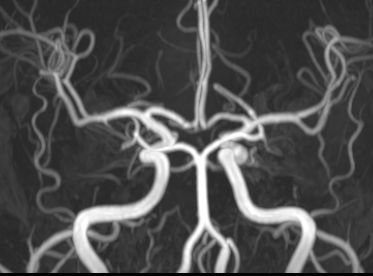

头颅MRA未见颅内异常血管,但头颅MRI-TOF像可见左侧天幕缘异常血管影(图2),CT薄层增强扫描见枕骨大孔区异常血管影(图3)。于2017年12月25日局麻下行全脑及全脊髓血管造影,脊髓血管造影未见异常,双侧椎动脉造影未见异常,最后行左侧颈内动脉造影示脑膜垂体干供血的天幕区硬脑膜动静脉瘘,瘘口位于岩骨中内1/3,直接经桥脑中脑侧静脉、扩张的延髓周围静脉向脊髓前静脉引流(图4)。造影诊断:左侧天幕区硬脑膜动静脉瘘。

图2. MRA未见异常,MRI-TOF示左侧天幕缘异常血管影(箭头所示)